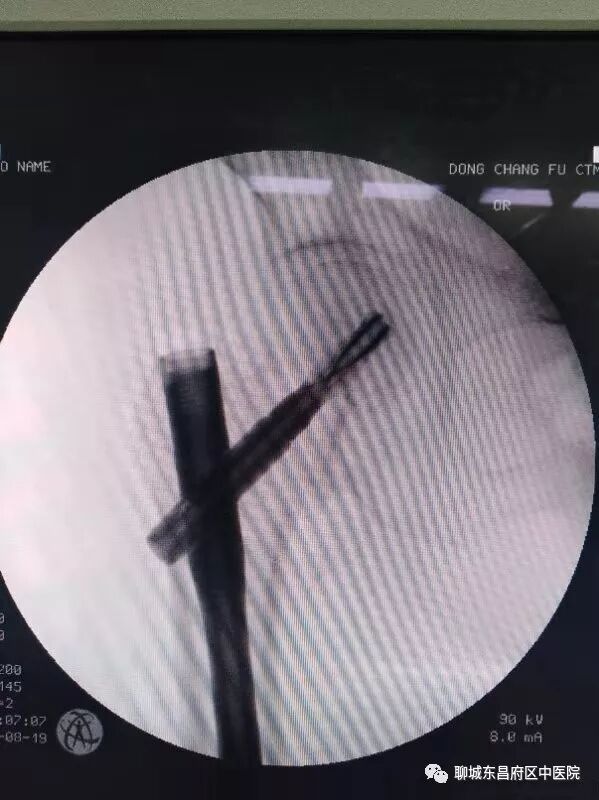

昨日,我院120接入一91岁高龄右股骨粗隆间骨折患者,入院后骨一科主任郭文青高度重视,对患者进行了初步查体,组织科室进行了风险评估,完善了入院相关检查,请麻醉科韩青主任进行了术前会诊。 经过详细的术前准备后,今日上午给予闭合复位PFNA内固定。患者90余岁高龄,各脏器已经严重衰老,对麻醉及手术的耐受能力已经很差,这已经给麻醉师提出了很严峻的考验,再加上患者驼背畸形,这就给麻醉穿刺带来了更大的困难。但我院手术室的同事们并没有被困难吓到,而是迎难而上,以精湛的技术,凭着过硬的基本功,顺利的完成了穿刺、置管、给药,整个过程患者病情非常稳定。该例股骨粗隆间骨折的手术,对于主刀医生也同样存在很大的困难。其一,该骨折为粉碎性骨折,虽为粗隆间骨折,但接近股骨颈,在复位时股骨头容易旋转,导致闭合复位失败。其二,患者骨质疏松严重,骨皮质很薄,在操作过程中很容易出现新的骨折,这就要求主刀医生在操作过程中要更加细心,准确。郭文青主任利用中医整复技巧,首先顺利的完成了整复,而后郭主任每一步操作都必须准确到位,经过40分钟紧张有序的忙碌,顺利的完成了手术,整个手术过程患者病情稳定,无疼痛及不适,术后往ICU继续治疗。